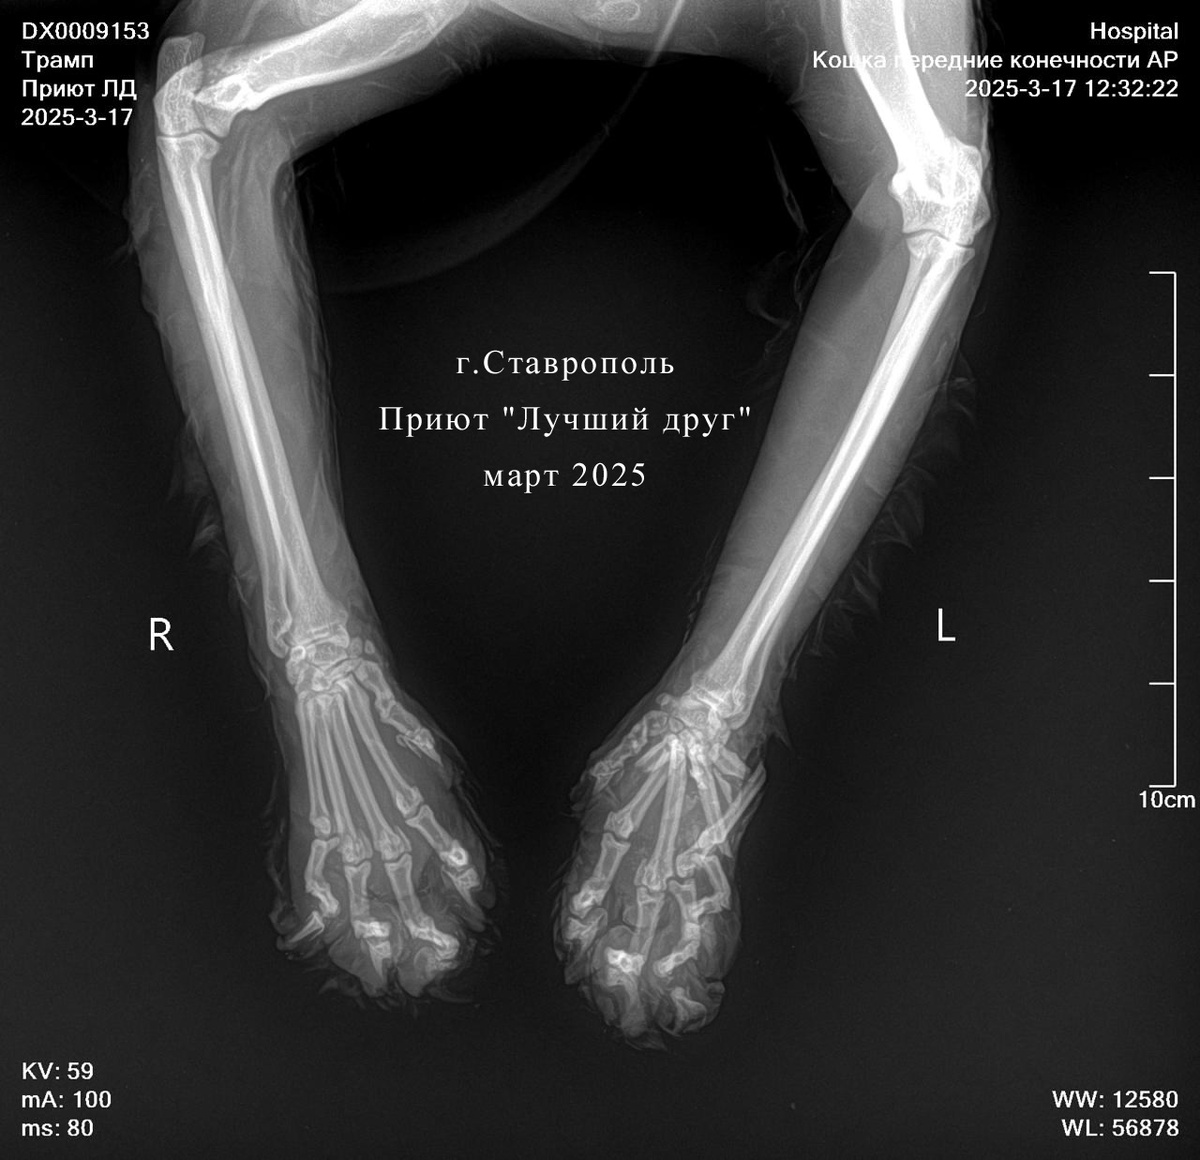

Самоуверенность подвела кота Трампа

Большой матерый кот обитал во дворах многоэтажек, выживал как мог, бился за свое место под солнцем и с конкурентами успешно справлялся. А потом он переоценил свои силы и попал в зубы пробегающей мимо собаке... Сам, к счастью, остался жив, но передняя лапа сильно пострадала. Волонтеры начали лечить кота на месте, но легче ему не становилось. С воспалением и отеком лапы кота отвезли в Ветцентр. С лапой всё очень печально, есть перелом фаланги, но оперировать нельзя из-за обширного некроза. Сейчас кот Трамп получает лечение на стационаре, прогнозы очень осторожные, но мы надеемся и верим, что брутальный красавчик скоро поправится и будет радовать нас басовитым мурчанием.